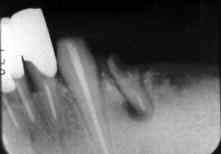

術前数年

歯周疾患 第3段階

術 前

歯周疾患 第4段階

ここ数年における骨吸収の進行から推測して1〜2年後には自然脱落するものと思われる

術直後

Fop+HAP骨補填材を施行し、周囲の骨レベルまでHAPを補填する

術後数年

ある一定量のHAPの残留を認めると同時に基底部付近での骨造成が推測される